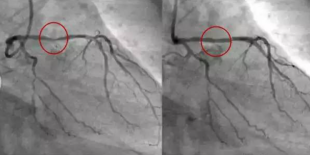

冠状动脉造影术(CAG)

冠状动脉造影术被誉为诊断冠心病的“金标准”。它通过细长导管从手腕的桡动脉插入,经过胸部到达冠状动脉,注入造影剂,并借助X射线实时成像,清晰显示冠状动脉的病变情况。这项检查的准确性非常高,能够详细呈现血管的解剖结构,明确显示是否有狭窄或阻塞。在发现病变严重时,医生可以直接在检查过程中进行介入治疗,如支架植入或血管扩张手术。因此,CAG不仅可以准确诊断冠心病,还能在同一过程中过进行治疗。

尽管如此,CAG是一种侵入性检查,存在一定的风险,包括出血、感染、血管损伤等并发症。此外,CAG相对于CTA来说,费用较高,检查时间较长,通常适用于症状明显或高风险的患者。尽管如此,它的精确度和治疗功能,使得它在诊断和治疗过程中仍然占据着非常重要的地位。